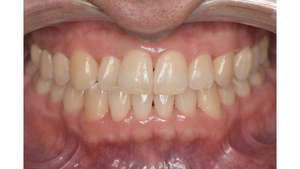

症例5

before

症例

after

基本情報

年齢・性別 32歳・男性

主訴 主訴:歯ぐきから出血する

治療部位:全顎

治療内容 「全顎」

歯周基本治療(歯周精密検査、スケーリング、OHI、SRP)

担当者所見 初診時は、写真を見て分かるように、歯ぐきが赤く腫れていました。

また、歯周病の検査では、全体的に歯と歯の間の部分の歯周ポケットが4ミリあり、全体の約81%から出血が認められました。

出血量も多く、歯ぐきに触れた瞬間に出血しました。

レントゲンで骨のレベルがしっかりとあることが確認できました。

そのため、ご自身で正しい歯磨きを継続することで改善すると考えました。

歯周基本治療を経て、再度検査した結果、歯周ポケットはほぼ3ミリ以下に改善しました。左下7番の残存した歯周ポケットは、隣の親知らずを抜いたため経過観察します。

出血率は約4%まで改善し、出血量も点状で少なくなりました。

今後は右上2番、右下3番の歯ぐきの発赤の改善と、出血率0%を目指して、定期検診でメンテナンスしていきます。